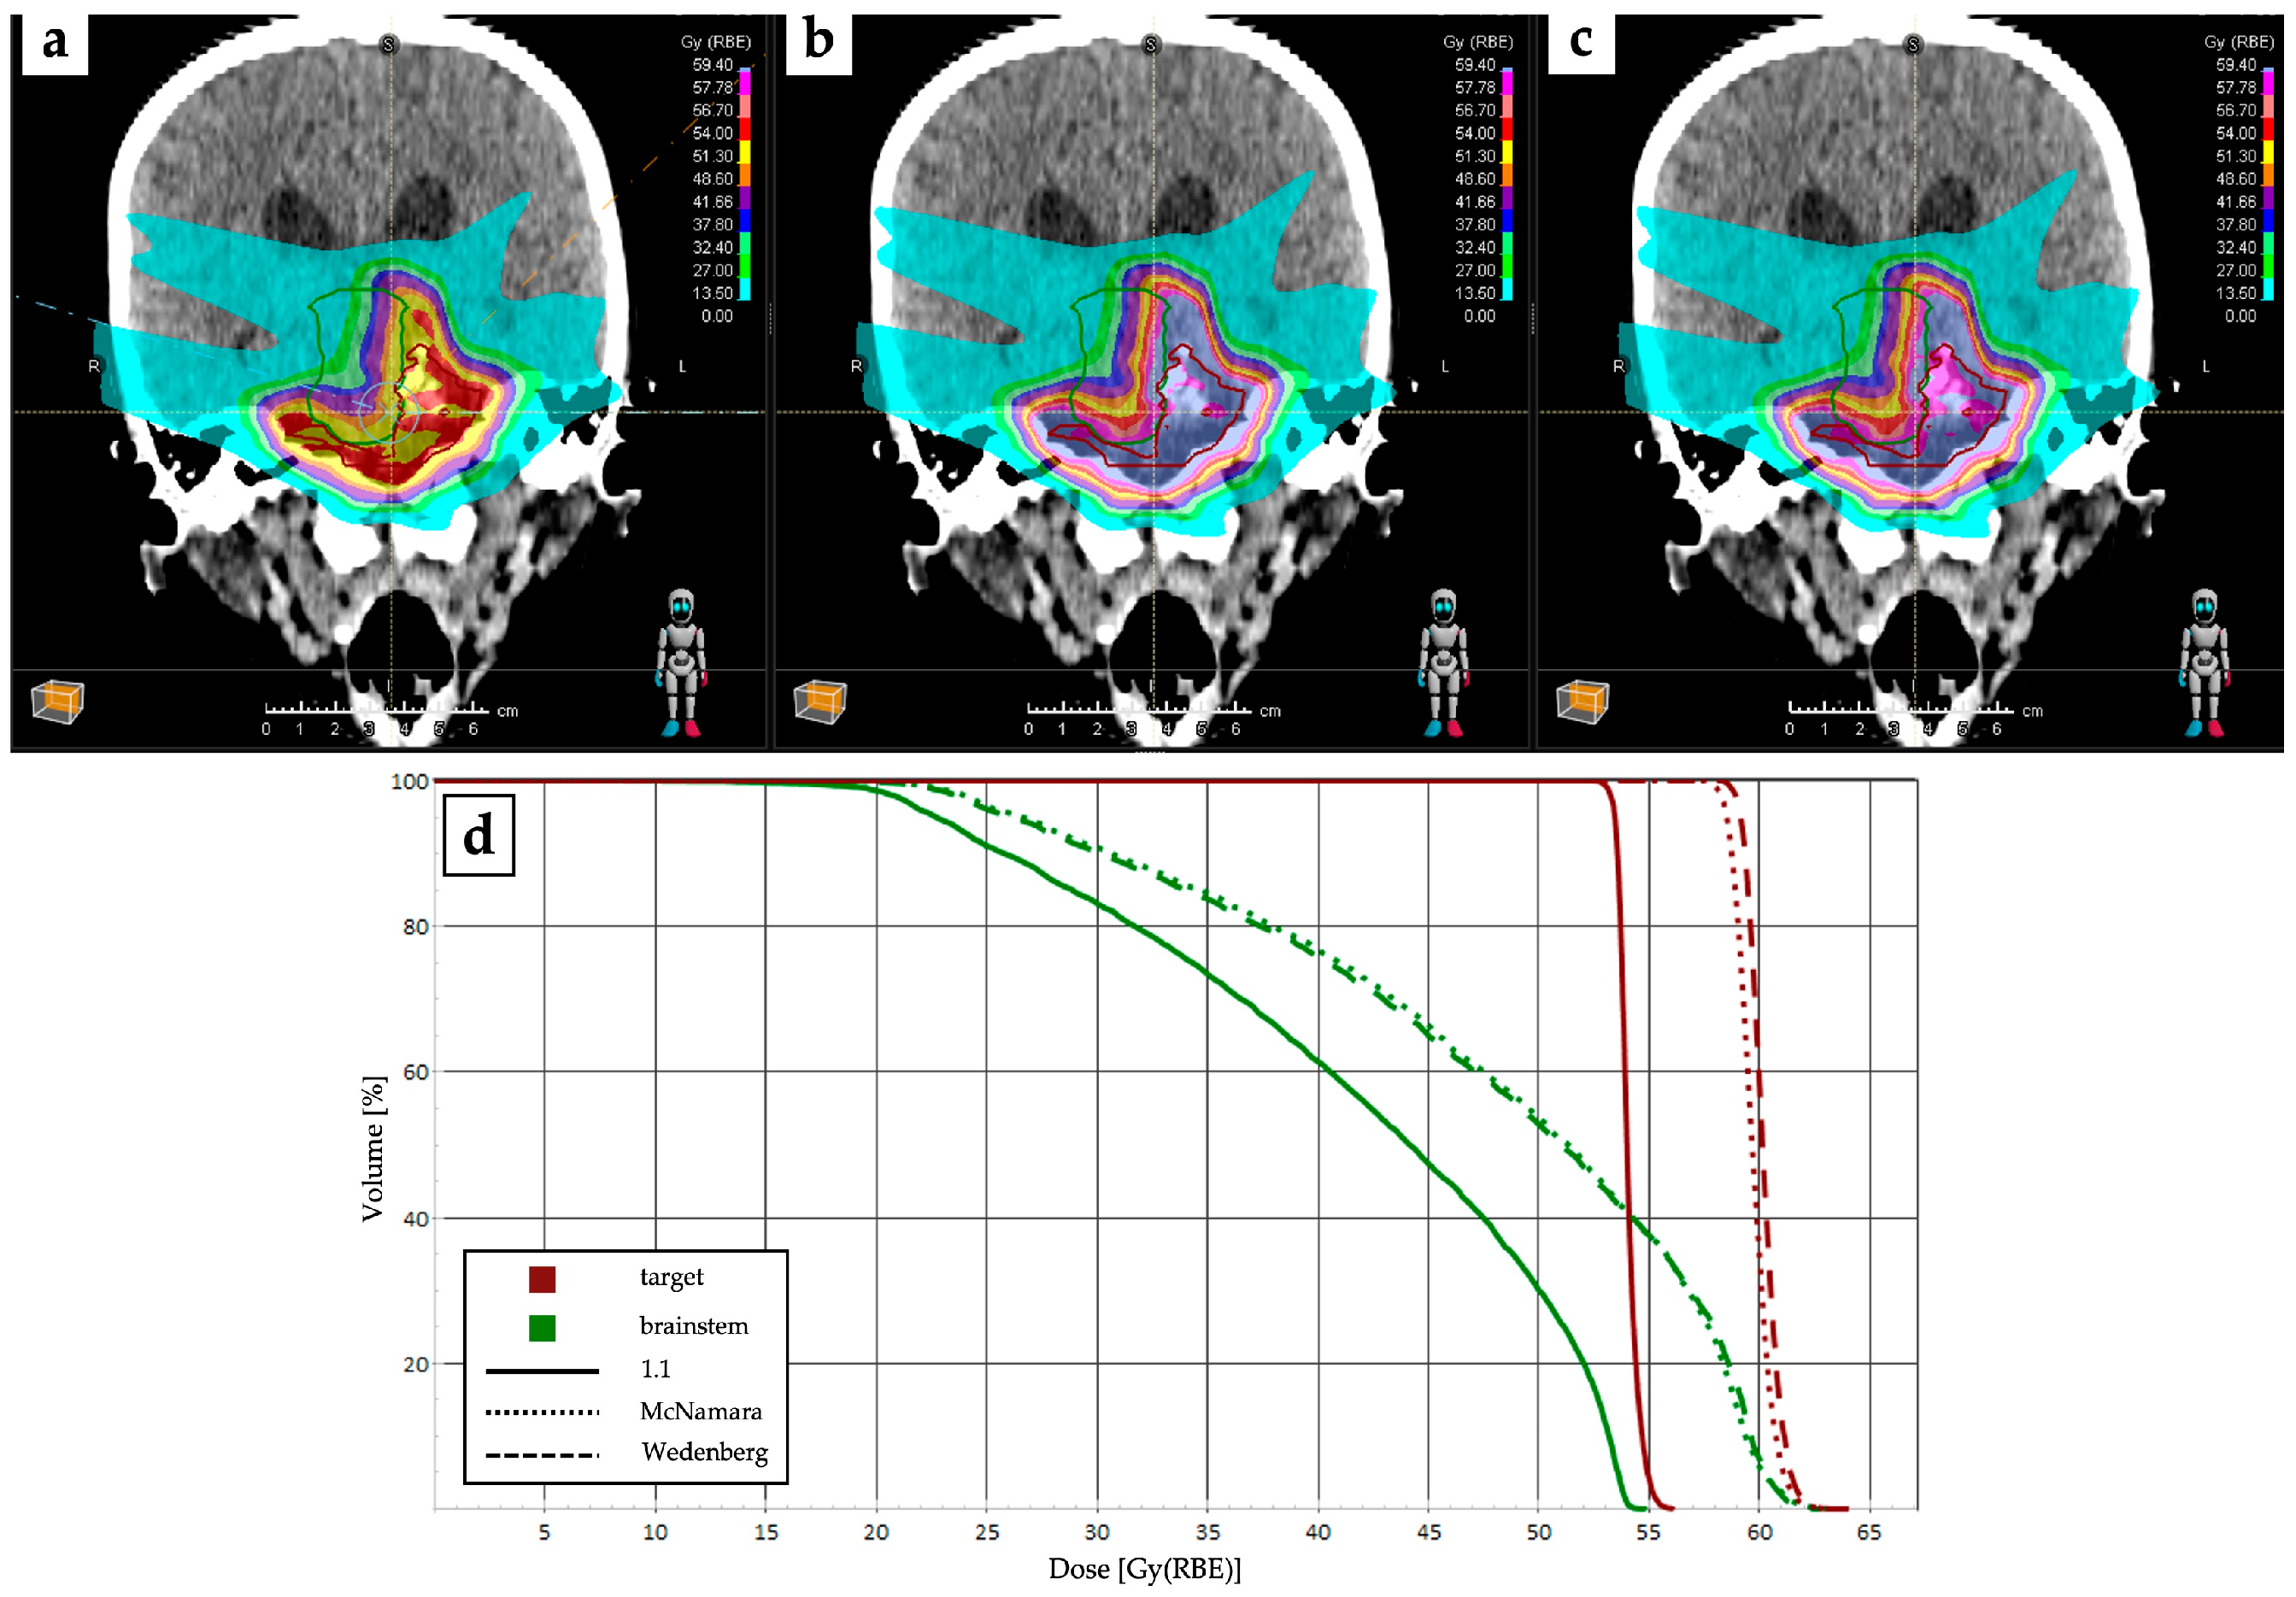

4.1. RBE and LET Optimization and Robustness Improvement